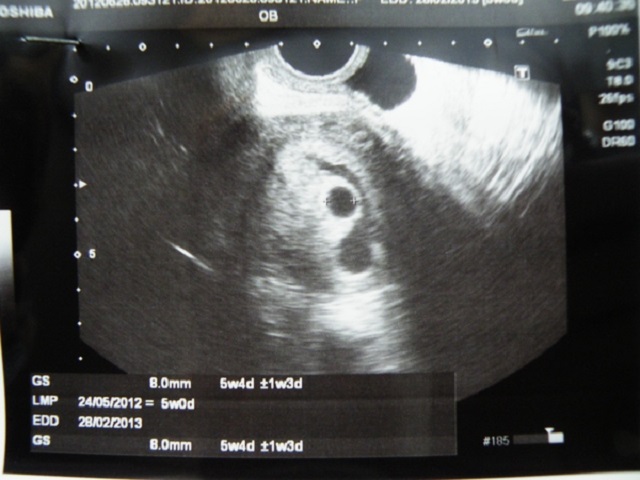

Результаты: УЗИ, КТГ, доплера, скринингаЧерез 11 дней после первого узи, пошла на повторное, посмотреть изменения и как поживает малыш. С малышом все хорошо, развивается по сроку, сб хорошее. Но, появилась уже вторая гематома внизу, гинеколог-узист сказала, что размеры не критичны, но сам факт появления уже второй гематомы её настораживает. Посоветовала сделать ТЭГ на свертываемость (ранее никогда проблем с кровью не было🤷♀️, но и гематом тоже не было).

Под кат фото и результат узи